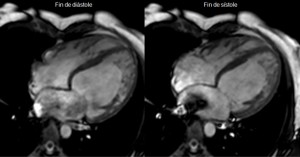

Resonancia magnetica cardiovascular corazón. La resonancia magnética cardiaca (RMC) es un una técnica de imagen para el estudio no invasivo del corazón, inocua ya que no utiliza radiación, bien tolerada y segura. Actualmente se encuentra disponible en la mayoría de hospitales. Permite estudiar en una sola exploración la función y estructura del corazón. Ofrece una imagen detallada del corazón, incluidas las cavidades y las válvulas. Está indicada para el estudio anatómico y funcional de cardiopatías congénitas, el origen anómalo de las coronarias, estudio de viabilidad y de perfusión del músculo cardiaco (con administración de contraste), estudios de función ventricular, estudio de miocardiopatías (enfermedades del músculo cardiaco), enfermedades del pericardio (capa de tejido que recubre al corazón) y masas cardiacas.

La resonancia magnética (RM) del corazón es un método imagenológico que usa imanes y potentes para crear imágenes del corazón y no utiliza radiación (rayos X).

Una resonancia magnética proporciona imágenes detalladas del corazón y los vasos sanguíneos desde múltiples planos. Con frecuencia, se emplea cuando se necesita más información después de que a usted le han hecho una ecocardiograma o una tomografía computarizada del corazón.